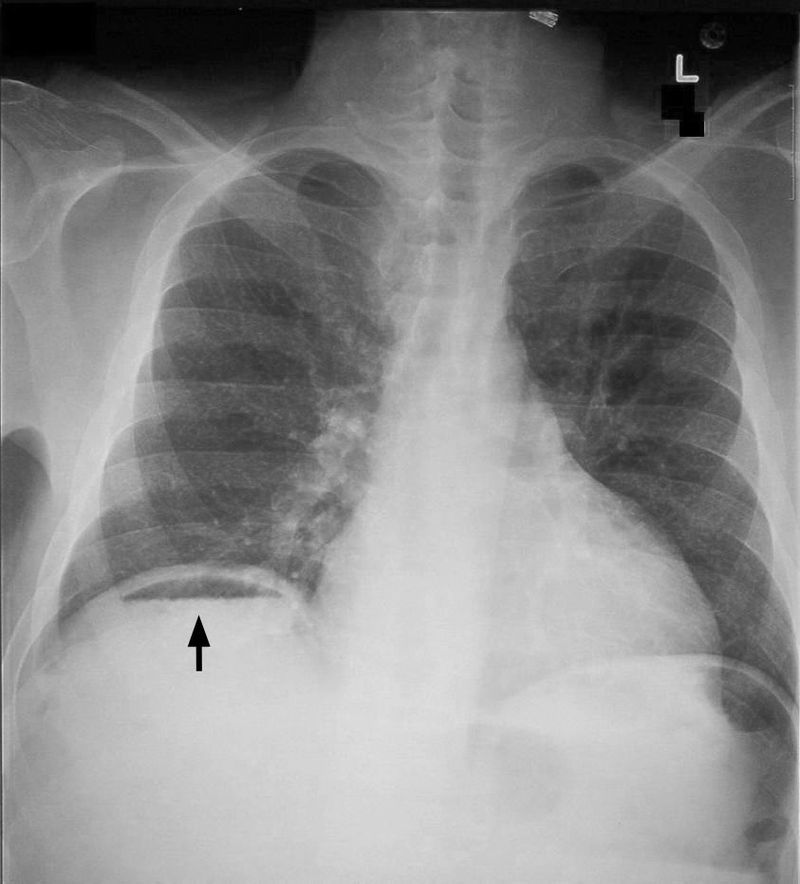

An erect CXR may also be required if a perforated peptic ulcer is suspected as the underlying cause. In such a case, air may be visible underneath the diaphragm (pneumoperitoneum).

What is shown in the image?

An erect chest radiograph, showing free air under the right diaphragm (pneumoperitoneum).